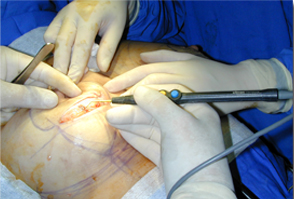

全新SURGITRON DUAL RF 120IEC,擁有更美的外觀,更強(qiáng)的性能,優(yōu)越的射頻止血功能,作為同時(shí)擁有4.0 Mhz和1.7Mhz的雙射頻產(chǎn)品,能應(yīng)用于更多的科室手術(shù)。